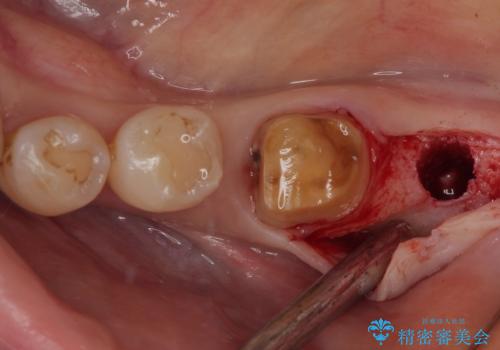

最後方歯は歯槽骨よりも深い部分にまでむし歯が及んでおり、患者様と相談の上、インプラントによる補綴治療を行うこととしました。

根尖部の病変が小さいことから抜歯即時埋入が選択されるところですが、抜歯窩洞が大きくなることと、窩洞直下に神経や血管が走行していることから、抜歯してから2,3ヶ月待機してから埋入することとしました。

手前の歯は、適合の悪いクラウンを最後方歯と同時にオールセラミッククラウンにて補綴治療を行うこととしました。